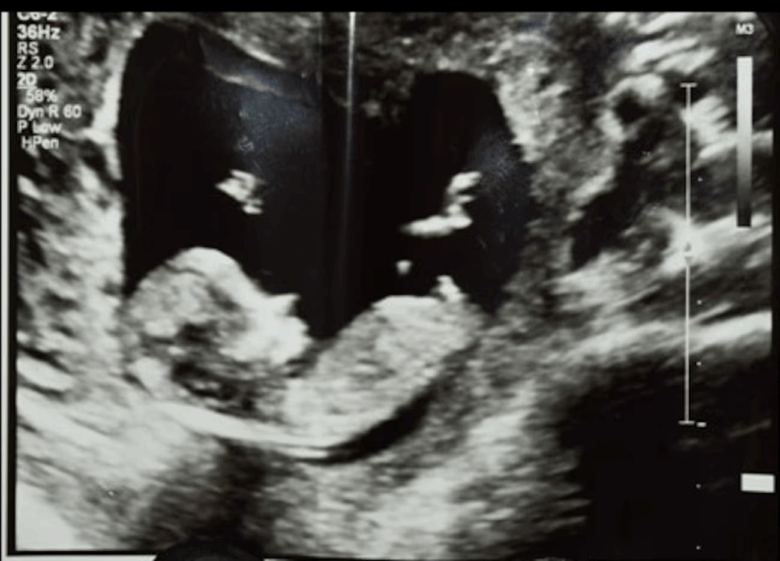

En la escena del crimen, los investigadores encontraron un casquillo de bala y una imagen de ultrasonido cerca de la víctima.